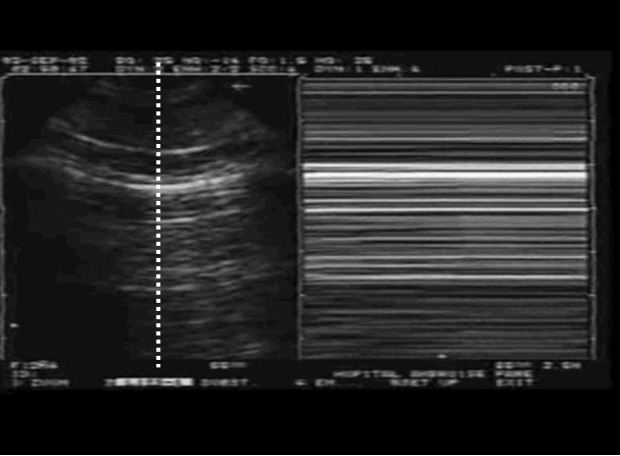

A线的出现代表胸膜线以下含气良好。胸膜滑动征消失的原因有多种,例如在胸膜粘连、肺不张、ARDS、重症感染后胸膜增厚等情况下可能会出现。2012年,重症医学相关研究人员发表的专家组文章指出,在怀疑气胸时,对胸膜滑动征的评估是起始因素,也是关键因素,对气胸的阴性预测值可达100%。也就是说,如果看到了胸膜滑动征,则可以排除气胸诊断;如果没有看到胸膜滑动征,还需进一步明确是否合并其他肺超征象,从而明确诊断。下列超声图像1中可见胸膜线随着呼吸运动而来回滑动,但在超声图像2中却未见胸膜线来回滑动。我们呼吸时,胸壁会被向上推开,当胸膜滑动消失时,可见胸膜线随着呼吸、肺扩张及胸壁向上移动。当看到滑动征消失时,需考虑气胸的可能。

超声图像2(无胸膜滑动)